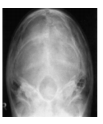

Assinale a alternativa que apresenta a imagem resultante de um posicionamento de PA de quadril.